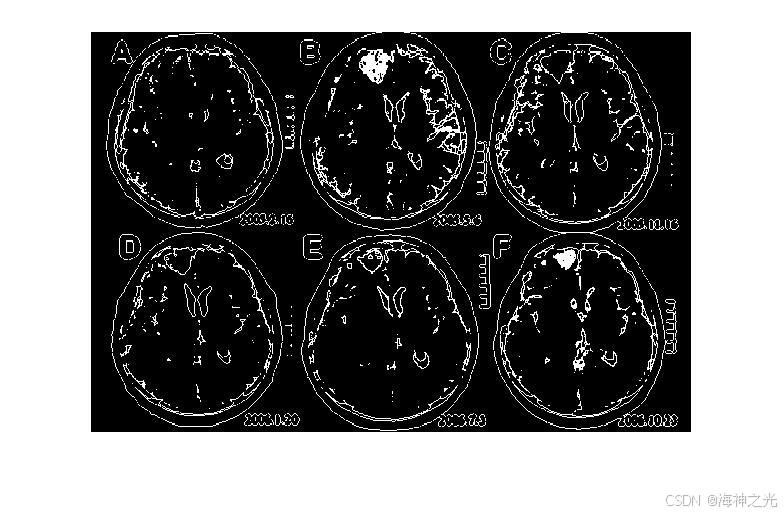

⛄三、运行结果